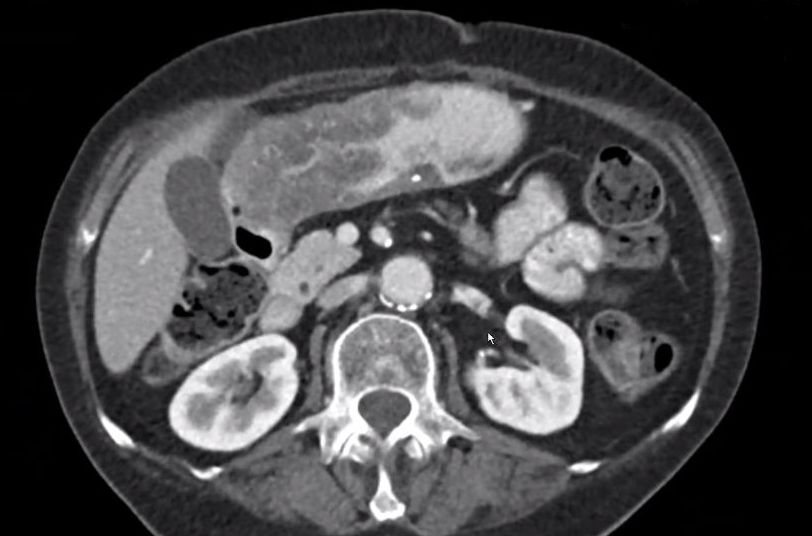

| AEG III | 72-jähriger Mann mit AEG III ypT2 ypN2(5/25) Mo. Intestinaler Bautyp.![]() | |||